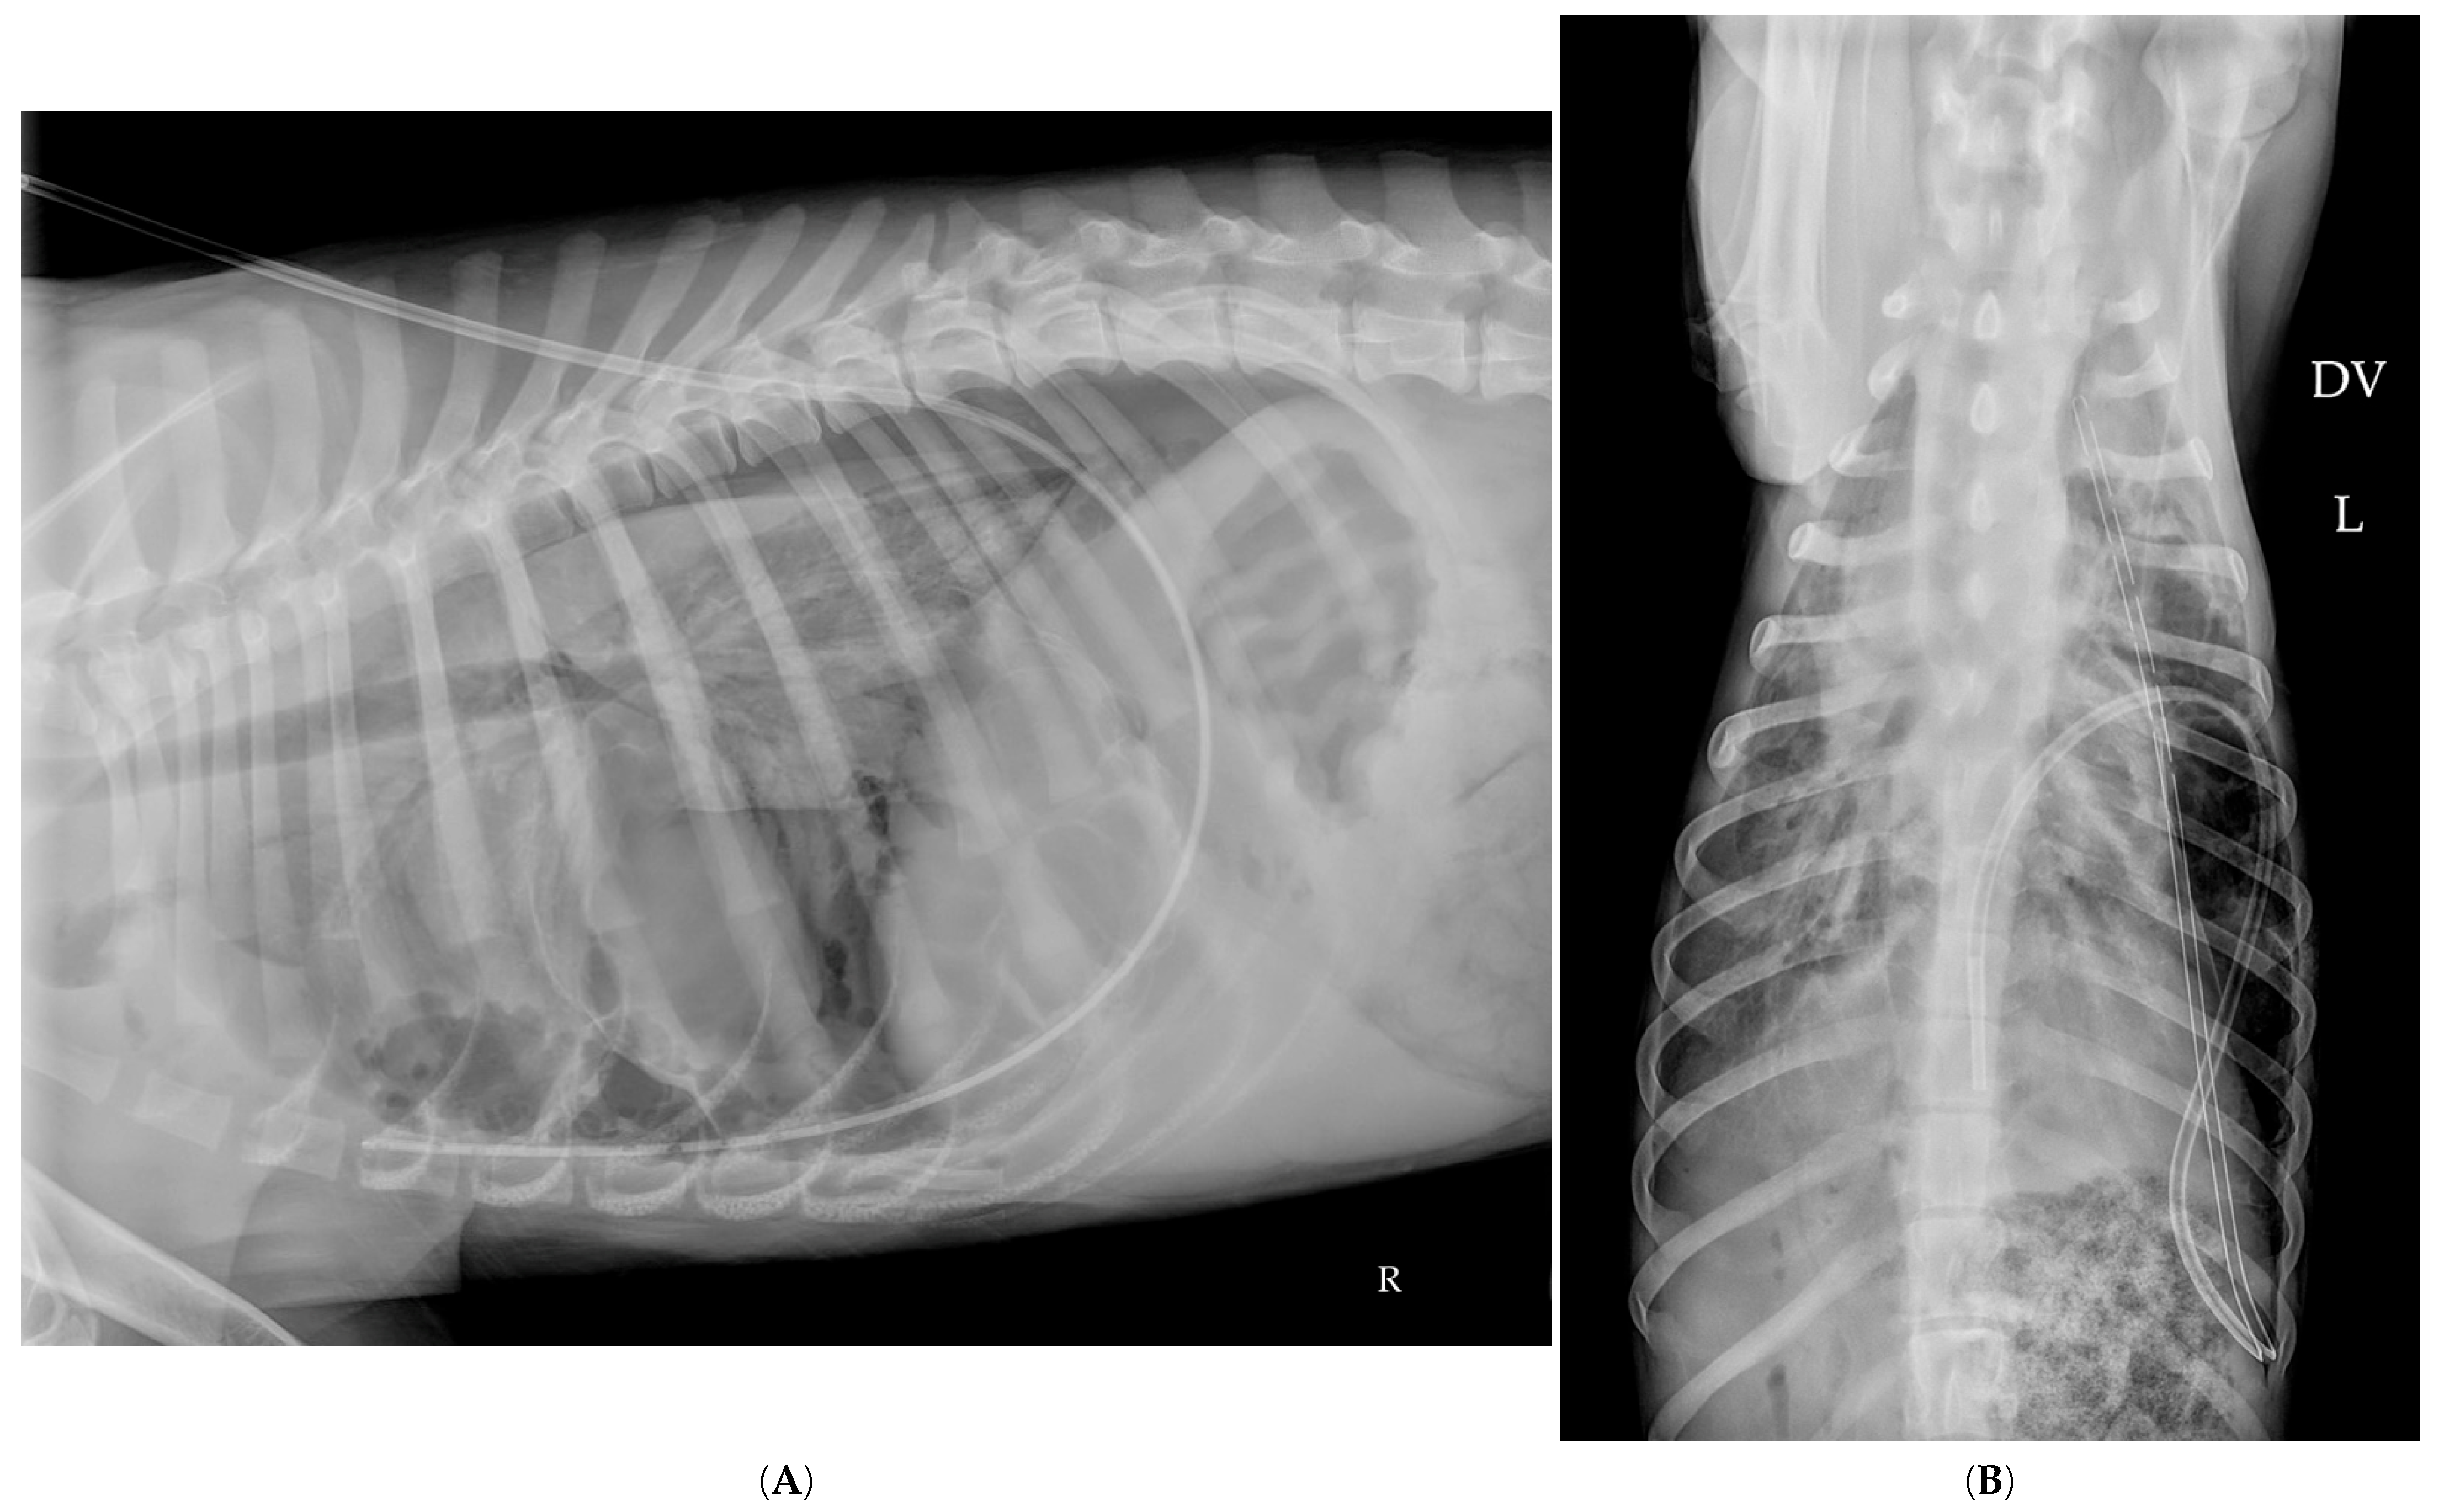

2.9. Thoracostomy Tube Placement

2.10. Hospitalization Follow-Up